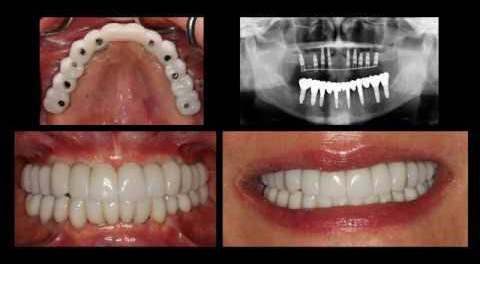

Implants:

Dental implants are placed to replace missing teeth

Crowns and Bridges:

Missing teeth can also be replaced by bridges, crowns, inlays etc., depending on the condition of your teeth.